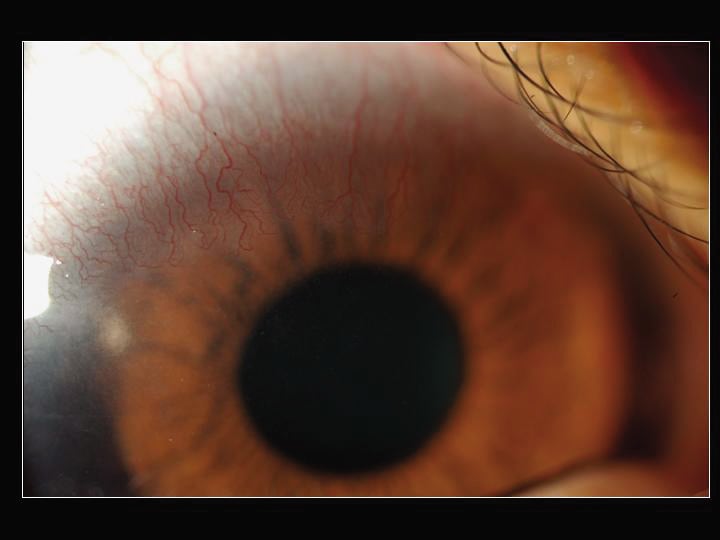

Figure 1. GS's left eye with mild bulbar injection. |

Slit lamp examination of the symptomatic left eye showed mild superior bulbar inflammation as well as significant superior neovascularization with lipid leakage (Figures 1 and 2). The superior corneal epithelium was irregular with small, elevated gelatinous nodules adjacent to the areas of neovascularization (Figure 3). We also noted significant punctuate staining confined to the superior one-third of the cornea.